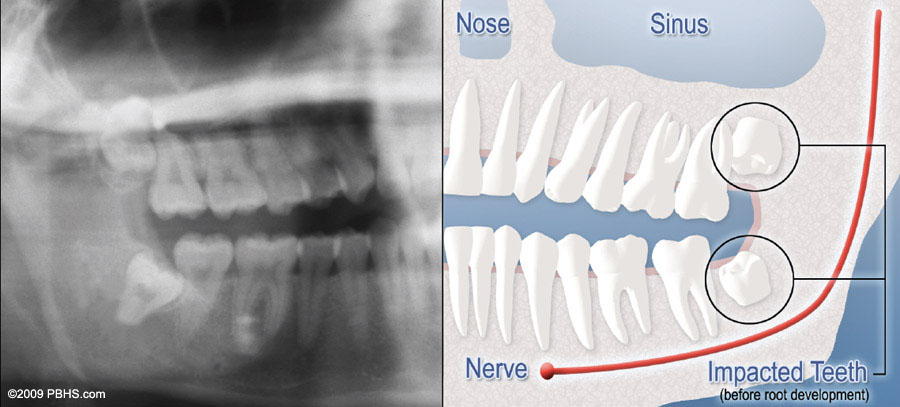

We will need to see you for a consultation to determine if you will benefit from wisdom tooth removal. A special x-ray of your mouth and jaws (panorex) will be taken to determine if your wisdom teeth are impacted, if there is room for them to erupt, and how difficult it will be to have them removed.

wisdom tooth soft tissue impaction

Soft Tissue Impaction

There is not enough room to allow the gum tissue to retract for adequate cleaning of the tooth.